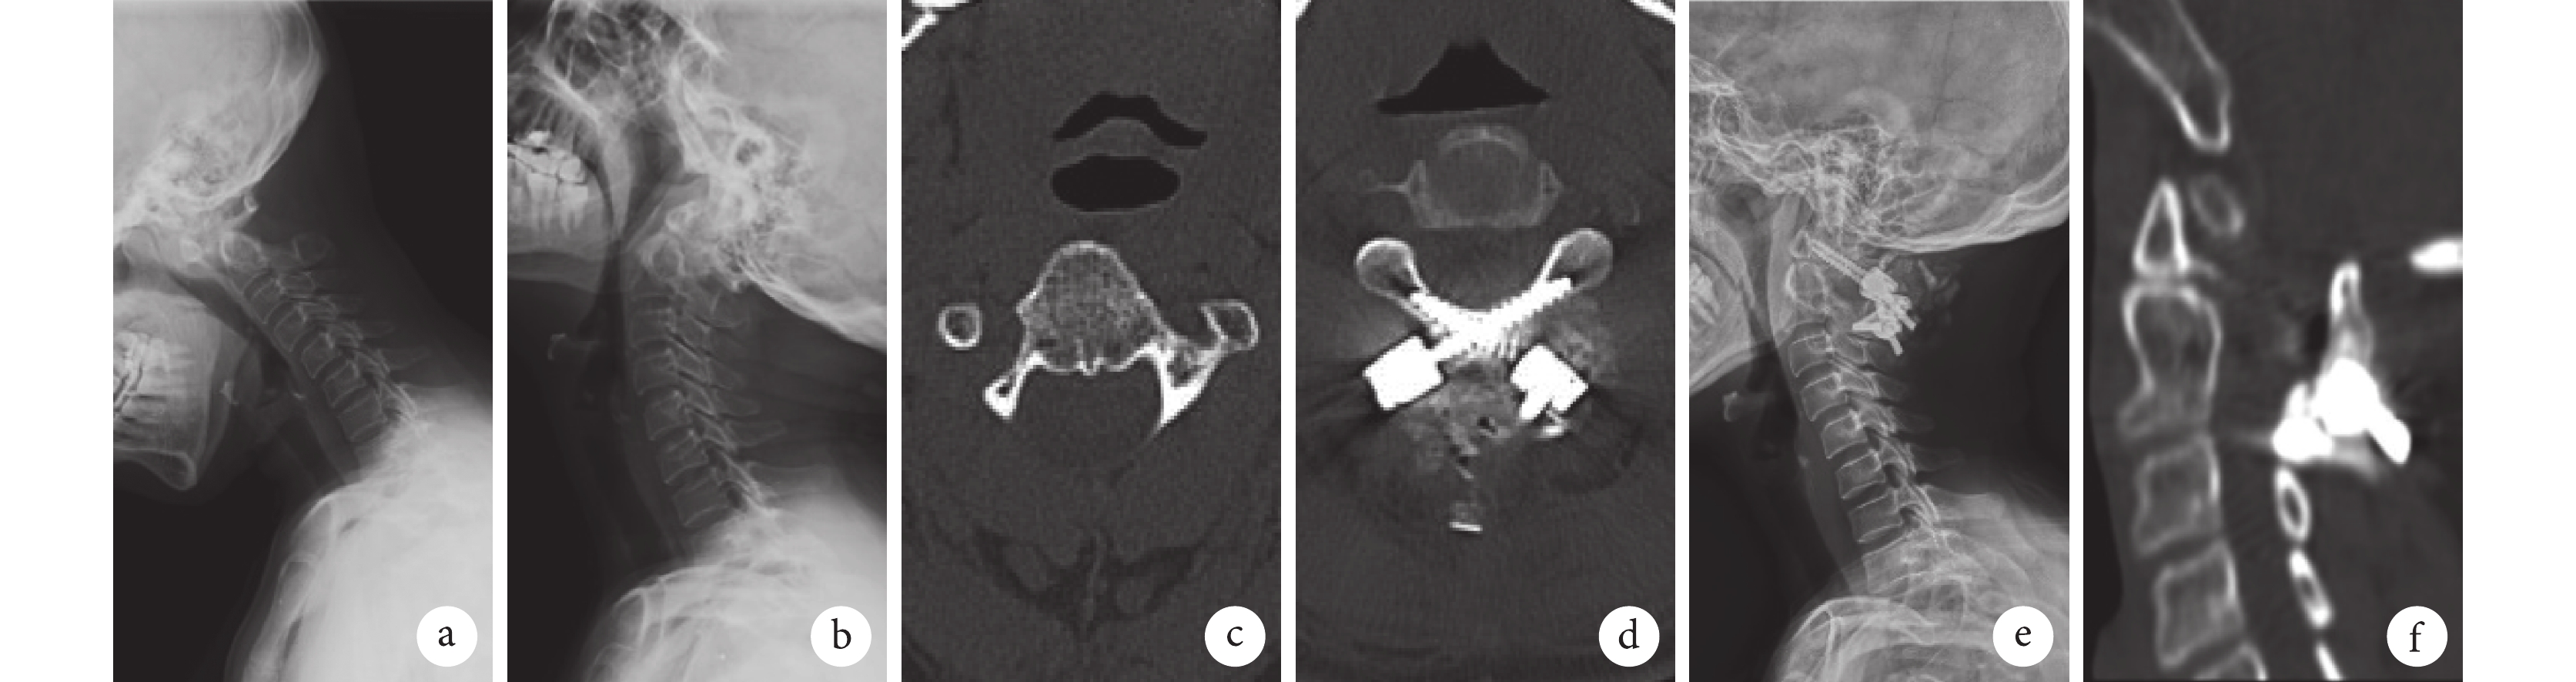

a、b. 術前過屈、過伸位 X 線片;c. 術前 CT 示樞椎右側椎弓根細小;d. 術后 3 d CT 顯示樞椎采用雙側椎板釘固定,樞椎螺釘位置準確;e. 術后 3 d 側位 X 線片示寰樞椎脫位已復位;f. 術后 12 個月 CT 示寰樞椎后方骨性融合

Figure1. A 51-year-old female patient with RAAD in LS groupa, b. Flexion and extension lateral X-ray films before operation; c. Preoperative CT showed the right axial pedicle was narrow; d. CT showed that the axis was fixed by the lateral laminar screws and the screws’ position were accurate at 3 days after operation; e. Lateral X-ray film showed the reduction of RAAD at 3 days after operation; f. CT showed the bony fusion of posterior atlantoaxis at 12 months after operation